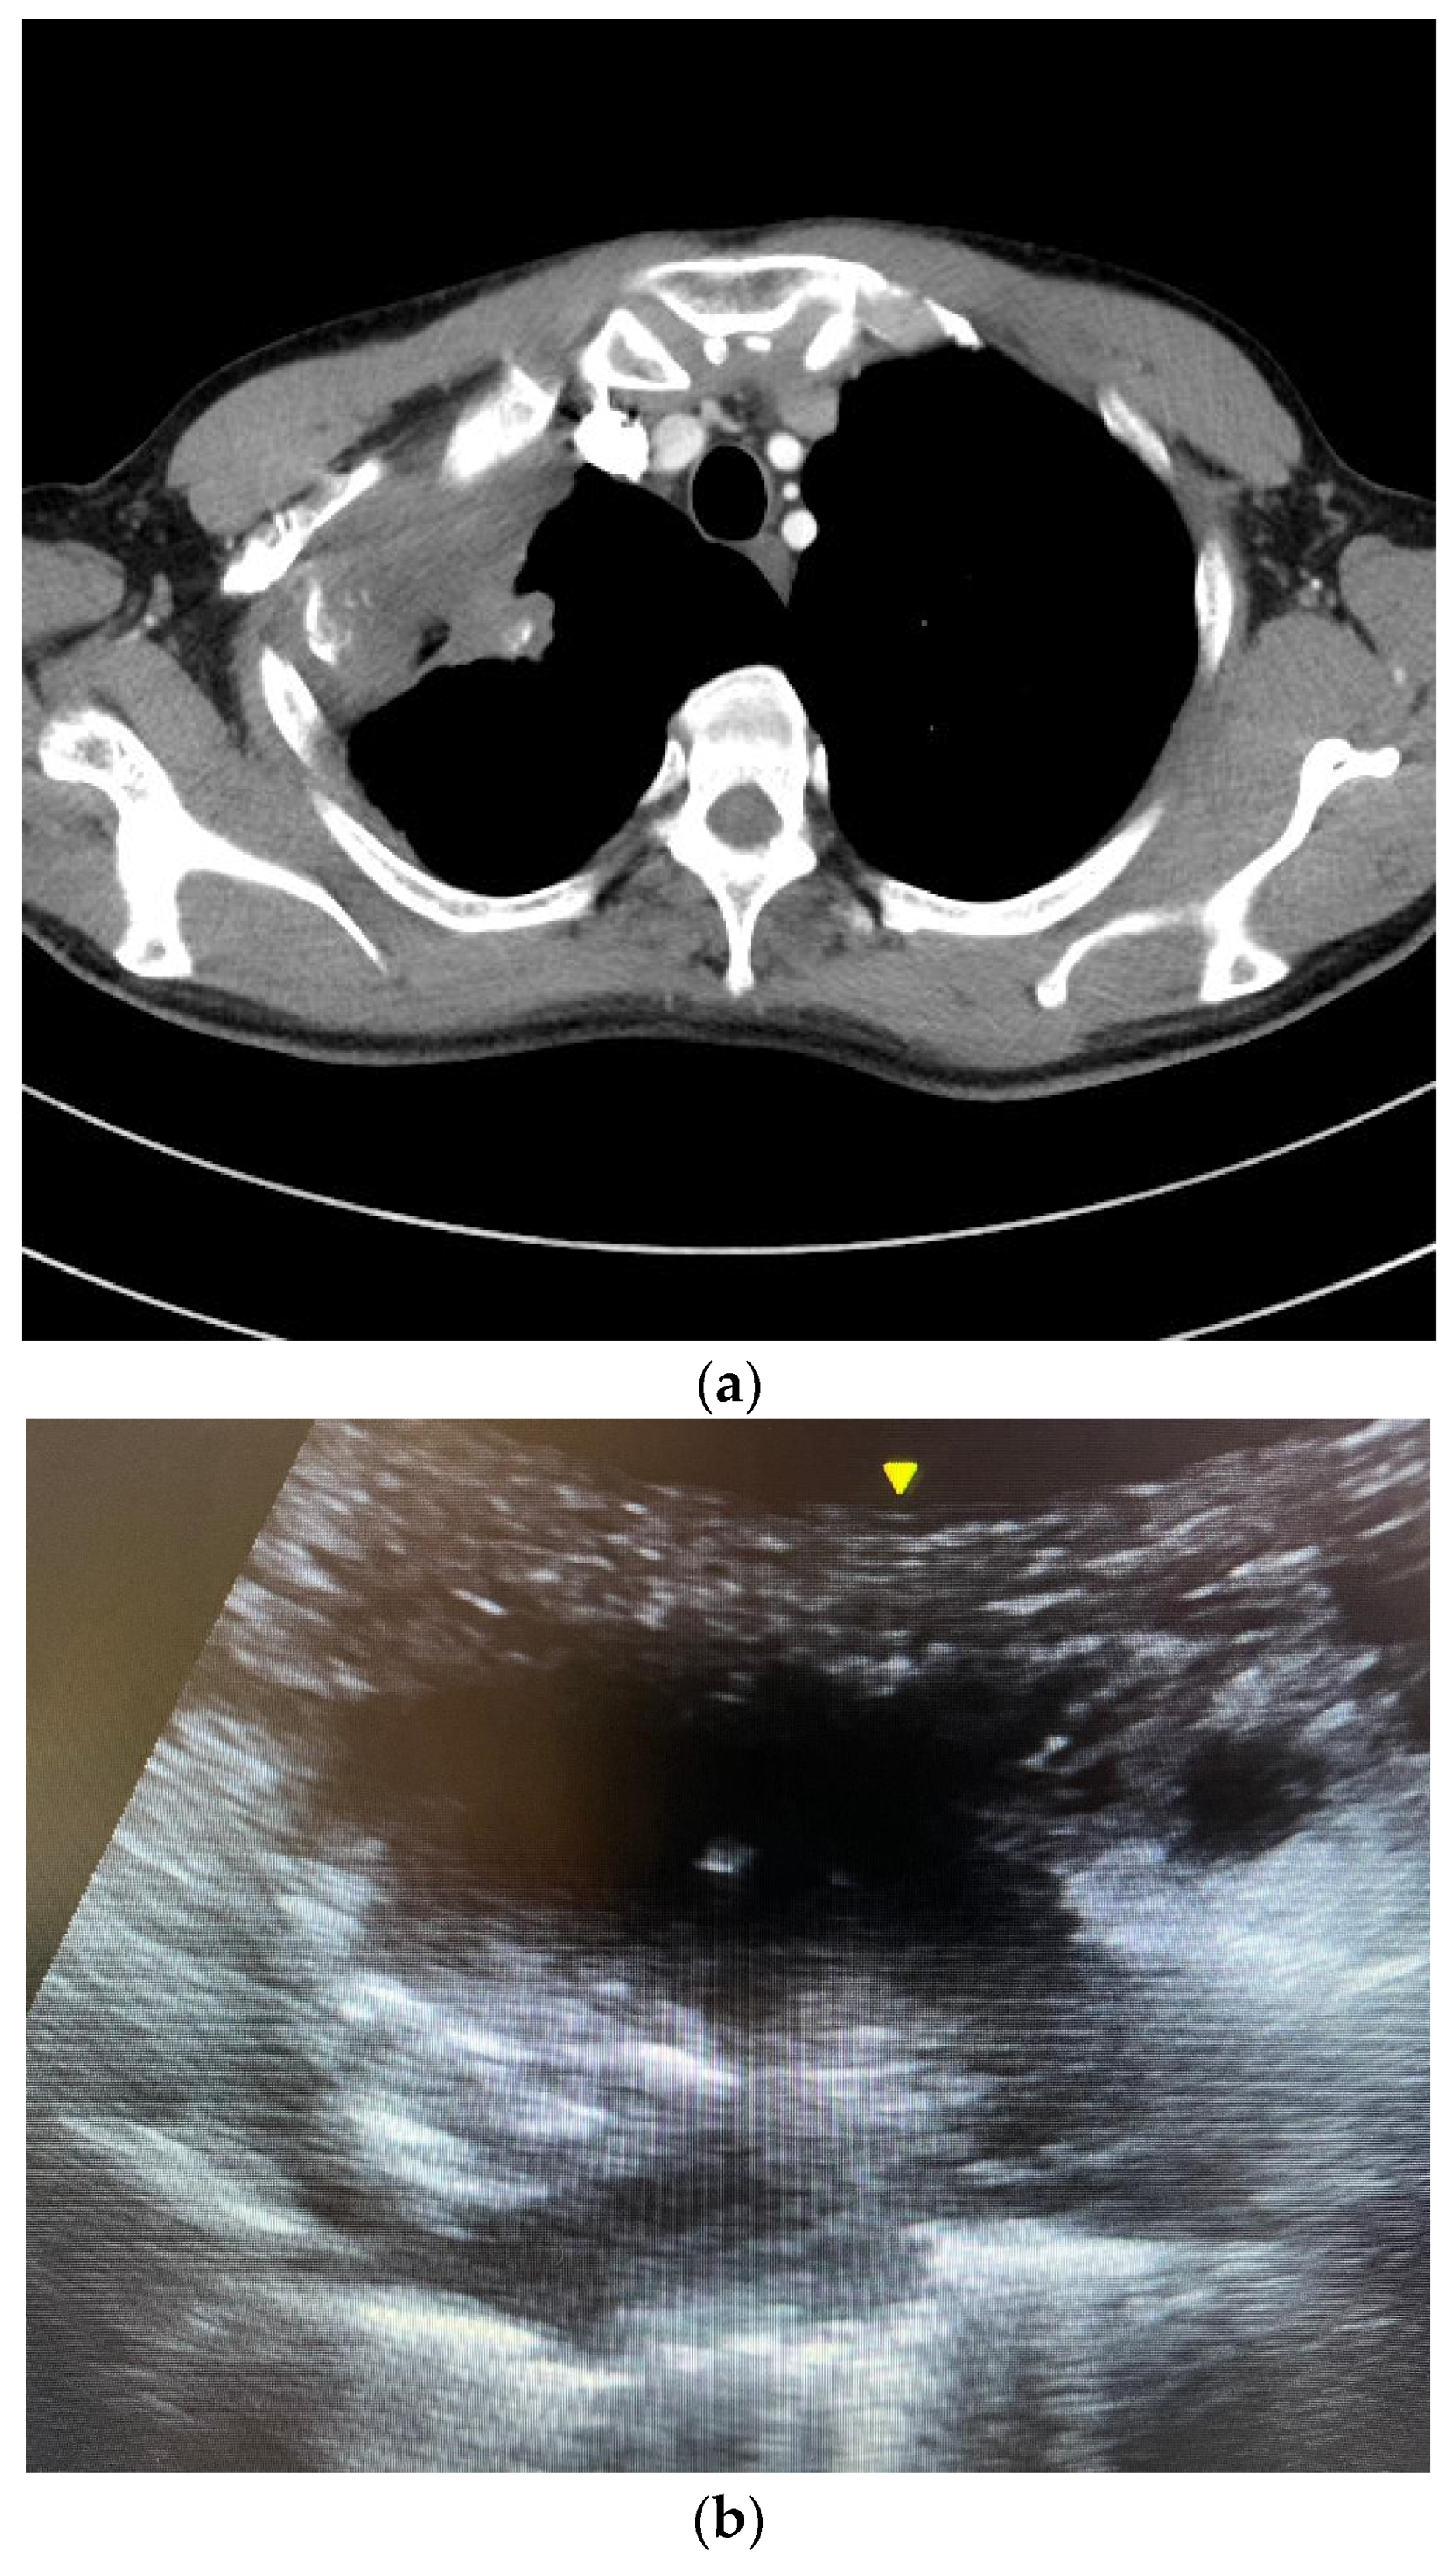

2.4. The Ultrasound-Guided Fine-Needle Aspiration